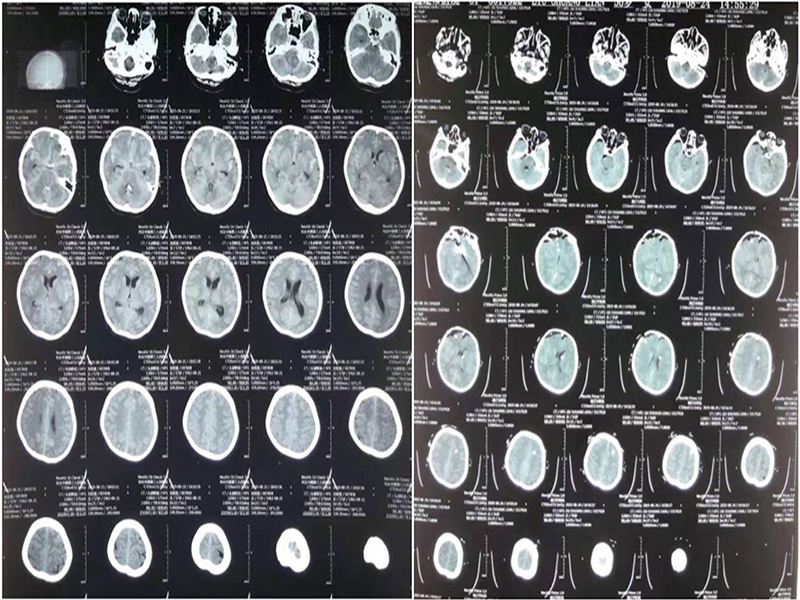

CT ()